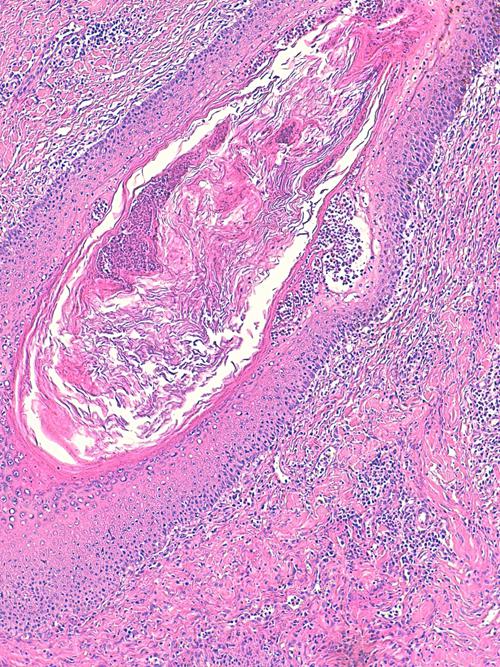

Photo 13 (Hémalun Eosine X 100) peau velue : dans le derme, de nombreux

follicules pileux sont rompus doannant naissance à des foyers furonculeux.

Légendes de la Photo 13 :

- Étoiles noires : infiltrat inflammatoire dermique et effondrant le follicule pileux

- Double flèche pointillée noire : gaine épithéliale externe du follicule pileux

- Ronds marrons : tige pilaire

- Flèches jaunes : rupture du follicule pileux (furonculose)